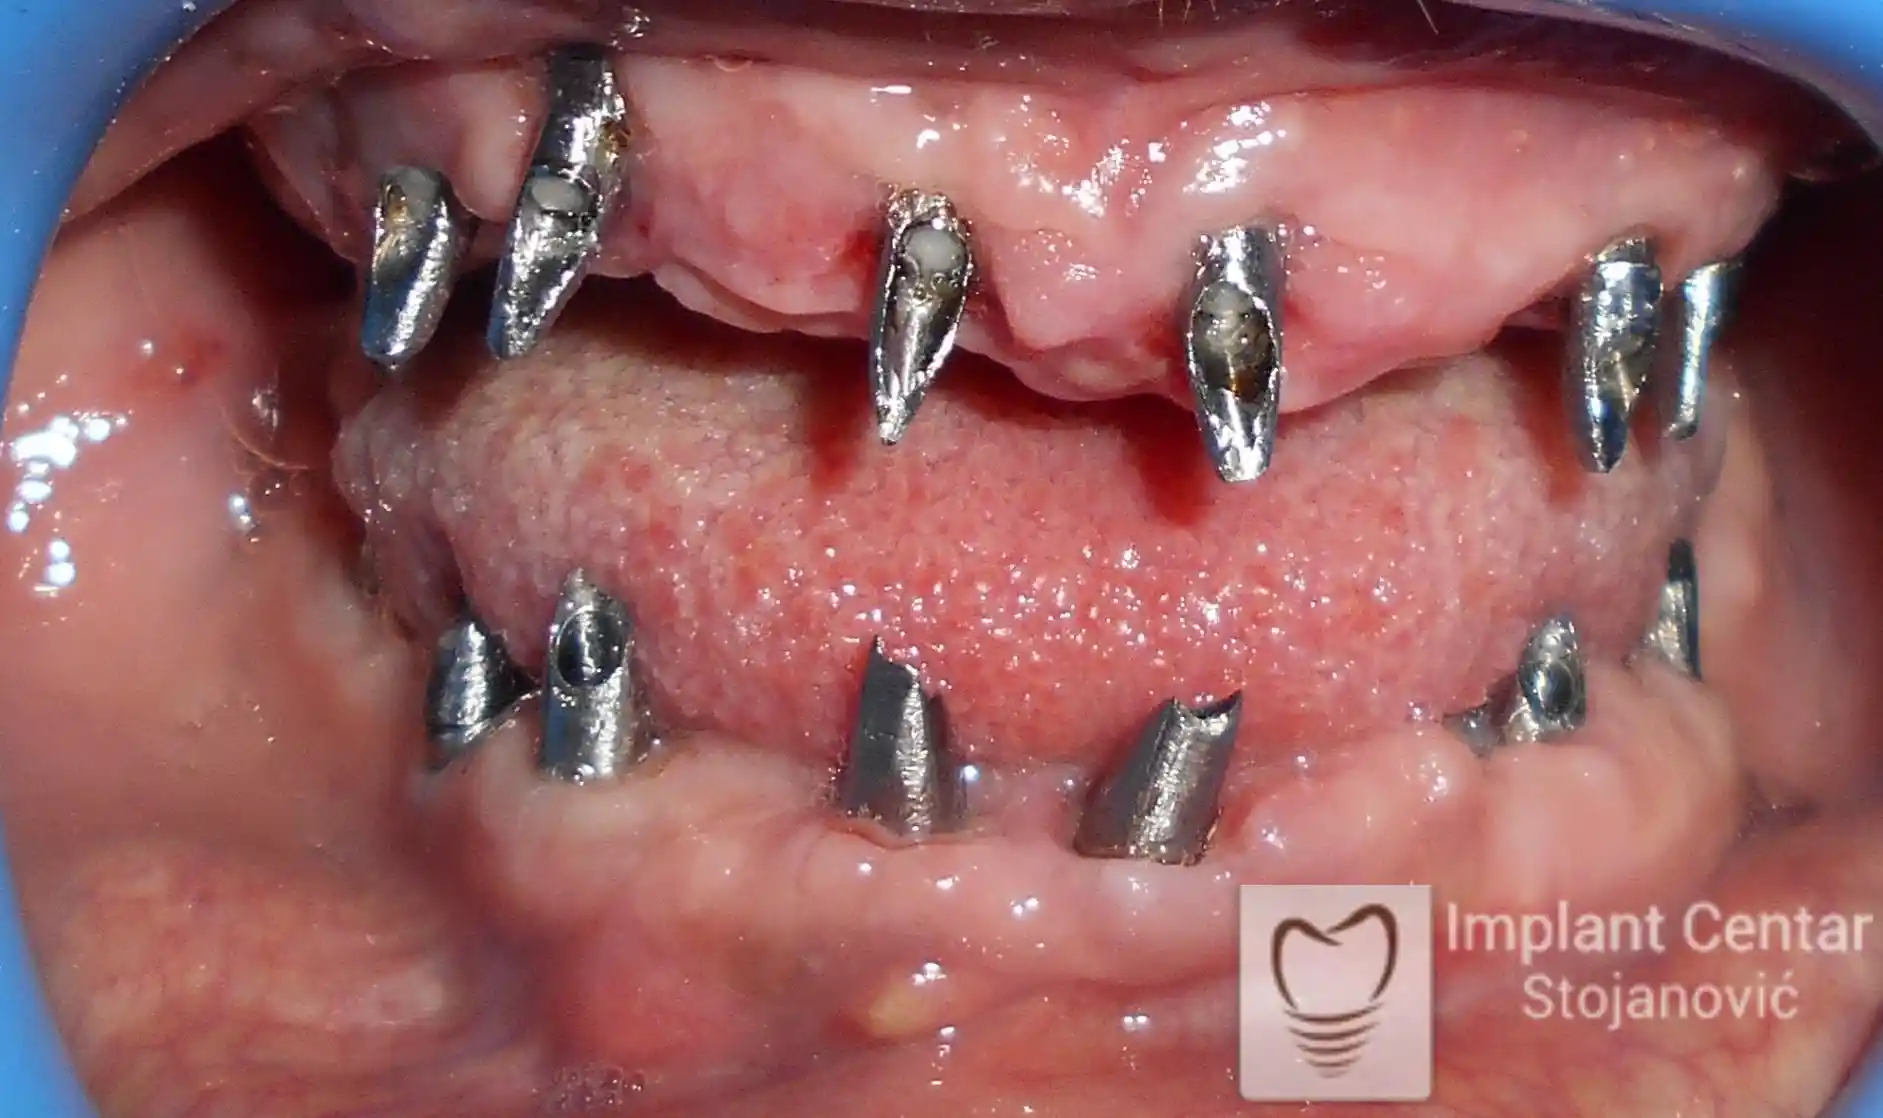

Nakon detaljnog kliničkog pregleda i analize radioloških snimaka, izrađen je sveobuhvatan plan terapije sa ciljem uklanjanja mobilnih proteza i postizanja maksimalne funkcionalne i estetske rehabilitacije. Zbog loše biološke vrednosti preostalih zuba, doneta je odluka o njihovom vađenju i ugradnji dentalnih implantata.

Poseban terapijski izazov predstavljalo je premošćavanje defekta nastalog usled rascepa, kao i ograničena količina raspoložive kosti u gornjoj vilici. Primenom većeg broja implantata i odgovarajućih procedura nadoknade kosti, postignuta je stabilna osnova za fiksni protetski rad.

Tokom perioda oseointegracije, pacijent je bio zbrinut fiksnim privremenim krunicama, čime je već pet dana nakon intervencije obezbeđena potpuna funkcionalna i estetska rehabilitacija. Nakon završetka perioda integracije implantata, izrađeni su definitivni cirkonijum-keramički mostovi na implantatima.